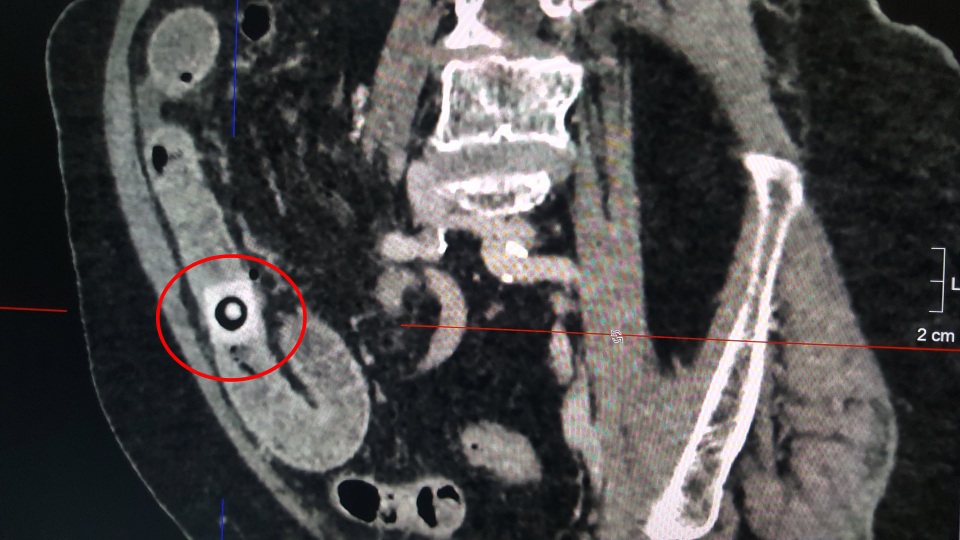

Dị vật là viên thuốc can quang, đâm thủng ruột non của bệnh nhân

Qua thăm khám và kết quả chụp CT các bác sĩ chẩn đoán cụ bà bị viêm phúc mạc khu trú, thủng ruột non do viên thuốc còn nguyên vỏ. Ngay sau đó, người bệnh được chỉ định mổ cấp cứu lấy dị vật. Trong lúc mổ, ê kíp tiến hành mở ruột non ngang qua lỗ thủng, lấy viên thuốc còn nguyên vỏ ra ngoài. Vị trí ruột non bị đâm thủng của người bệnh được bác sĩ khâu lại, đồng thời hút rửa sạch ổ bụng, điều trị kháng sinh tích cực chống nhiễm trùng.

Sau khi thăm khám, bác sĩ ghi nhận ông có dấu hiệu khó thở do nhiễm trùng. Thăm khám phổi thì phát hiện thấy có bất thường ở phổi nên bác sĩ tiến hành chụp X-quang, CT ngực, kết quả phát hiện dị vật ở 2 vị trí phổi bên phải. Bằng phương pháp nội soi ống mềm, các bác sĩ đã lần lượt lấy ra một viên thuốc còn nguyên vỏ bọc có kích thước 1,5x1,5cm và đầu cây tăm tre kích thước 10mm nằm sâu ở thùy dưới bên phải.